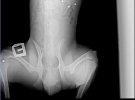

"Рентген показал более 10 пуль в его теле. В собаку стреляли, и неоднократно. Одна пуля застряла в позвоночнике, другие повредили внутренние органы, еще одна попала в лапу. Состояние критически тяжелое, задние лапы парализованы. МРТ сделать нельзя, потому что пули в теле не позволяют провести процедуру", - рассказали спасатели.